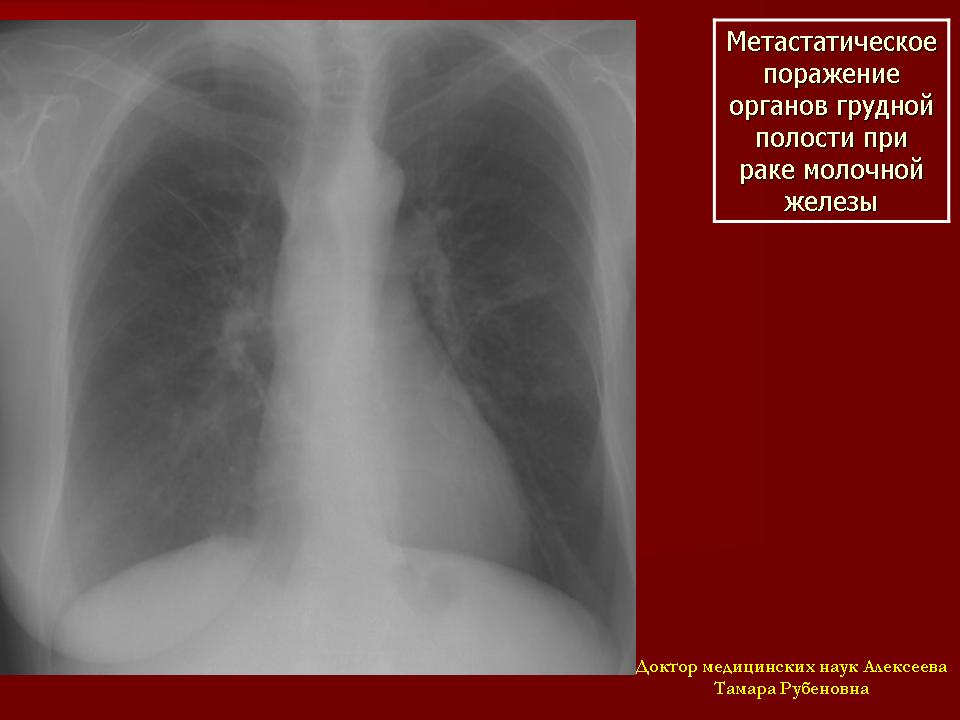

Метастатическое поражение органов грудной полости при раке молочной железы имеет самую разнообразную картину. Это разнообразие проявлений зависит от локализации опухоли в молочной железе и от тенденции опухоли к лимфогенному пути распространения. Пути оттока лимфы от молочной железы происходят в восьми различных направлениях. Однако опухолевые клетки их первичного очага разносятся не только лимфогенным, но и гематогенным путем. Поэтому при раке молочной железы может наблюдаться как изолированное поражение легочной ткани, плевры и лимфатических узлов средостения, так и их сочетание.

Наиболее часто выявляются гематогенные метастазы в легких в виде хаотично расположенных шаровидной формы образований средней интенсивности, однородной структуры, с четкими контурами, различных размеров от 0,3 см до 3,0-4,0 см диаметром.

Рис. 2а – обзорная рентгенограмма органов грудной клетки в прямой проекции: в легких с обеих сторон видно хаотично расположенные очаги и фокусы уплотнения.